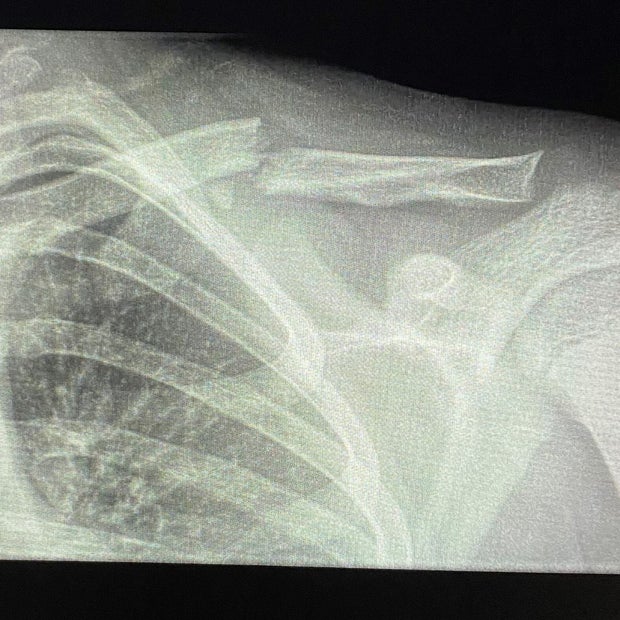

The teen has several injuries, including a broken clavicle due to the ski crash.